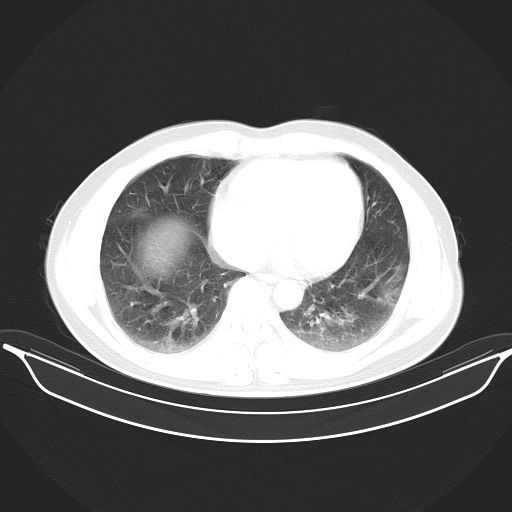

标题: CT25490:男,40岁,体检发现;无其它不适。 [打印本页]

标题: CT25490:男,40岁,体检发现;无其它不适。

考虑右下肺周围性肺癌并肺内多发转移,纵隔淋巴结转移!

支持 !考虑右下肺周围性肺癌并肺内多发转移,纵隔淋巴结转移,(气管前腔静脉后,隆突下,主动脉弓下都有了)